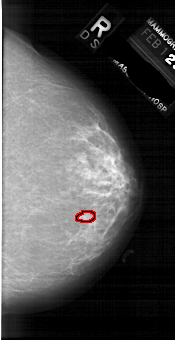

FILE: A_1739_1.RIGHT_MLO.OVERLAY

TOTAL_ABNORMALITIES 1

ABNORMALITY 1

LESION_TYPE MASS SHAPE LOBULATED MARGINS CIRCUMSCRIBED

ASSESSMENT 3

SUBTLETY 1

PATHOLOGY BENIGN

TOTAL_OUTLINES 1

BOUNDARY